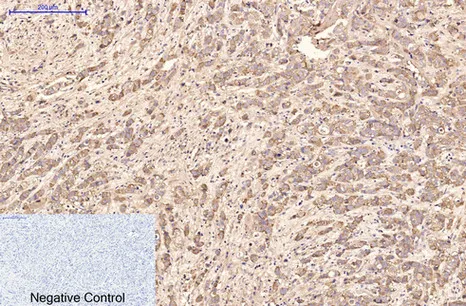

HER2(11H9)Mouse Monoclonal Antibody

Cat: AMM11986

Application:WB,IF-P,IF-F,ICC/IF,IHC-P

Reactivity:Human,Mouse,Rat